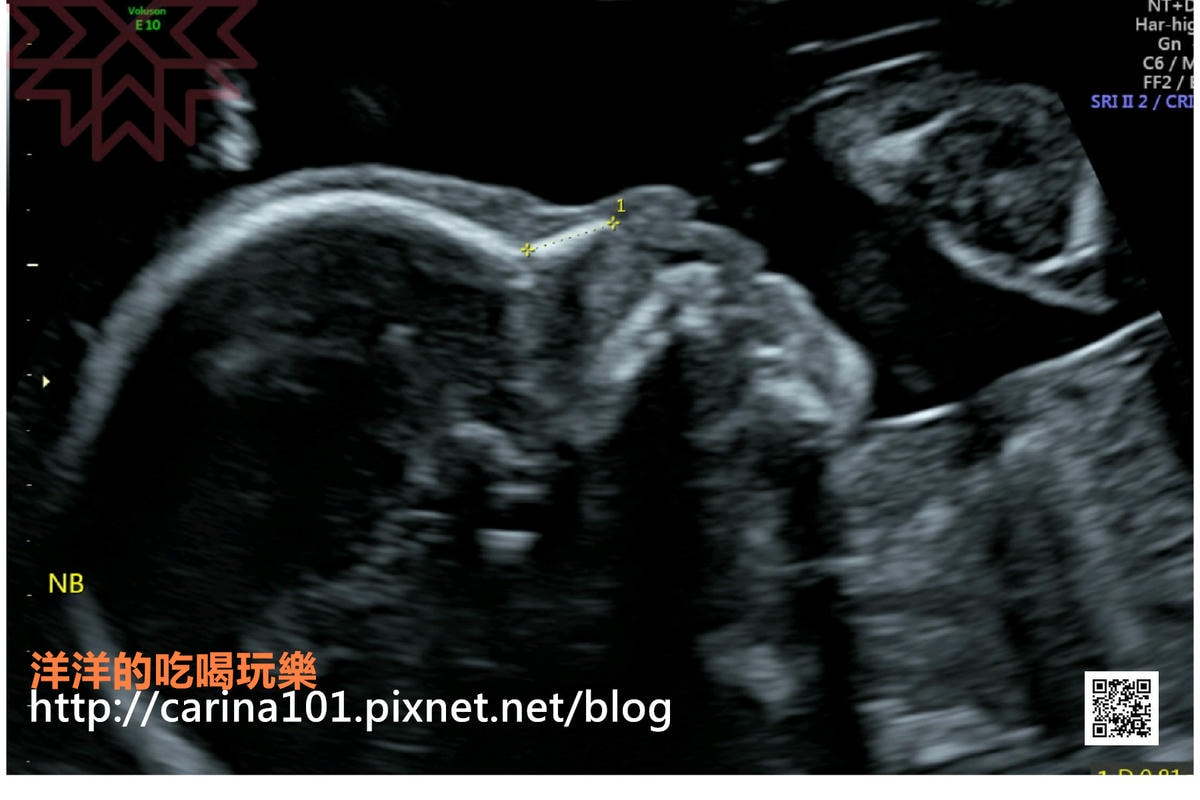

禾馨的超音波算有名的清楚

高層次會先由技師照一遍,然後再由醫生照一遍

還有此次超音波影像全部的彩色列印

就可以看到這次高層次超音波照片的電子檔

忘記那個超音波影像代表那個身體那個部位也沒關係

進到APP中的3D互動報告

選擇腳就可以跑出腳的超音波照片囉!